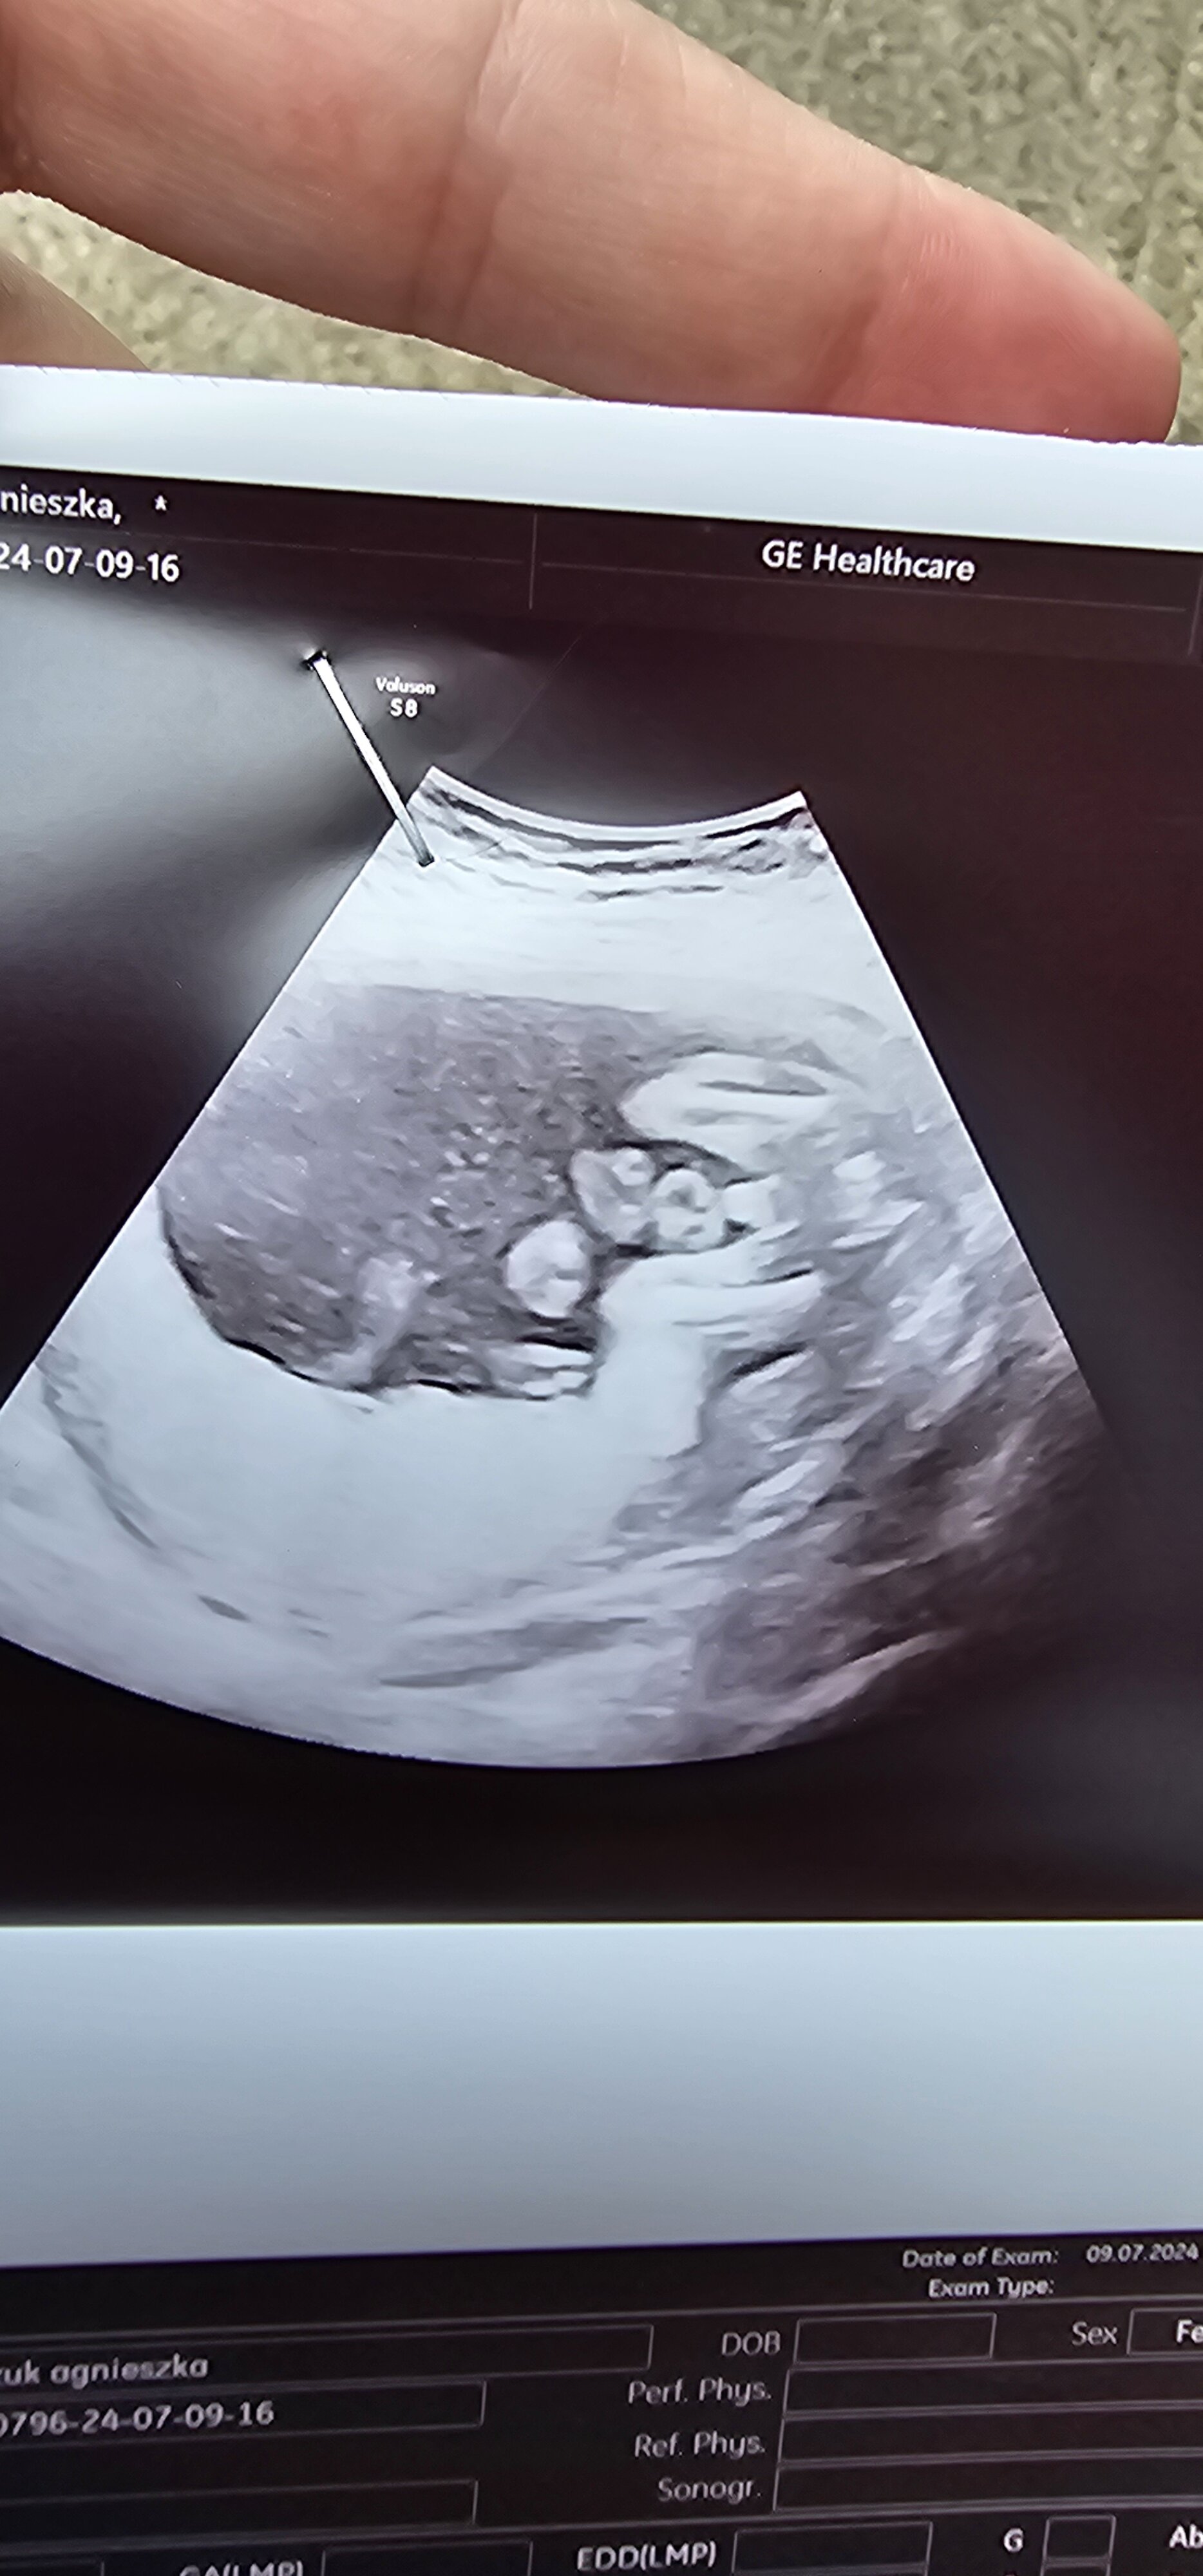

31 tydzień ciąży. USG chłopiec czy dziewczynka?

Z ostatniego USG mam tylko takie, chłopiec czy dziewczynka? ;)

Lekarzem nie jestem, ale dla mnie tu wyraźnie widać mosznę i to chłopiec

Bo tu faktycznie nie ma siusiaka ale według mnie jest moszna

Hej dziewczyny, nie mam pewności co do płci, na pierwszych prenatalnych nie chciało się pokazać kim jest , strasznie się zakrywało , dzisiaj ginekolozka powiedziała że chłopiec, a wy jak myslicie? 🙈 mam już córkę, ale nie mam żadnego zdjęcia z usg córki. Jak wy uważacie co tu widać? Dodam iż to 20tc i mam tylko takie zdjęcie

• 20240709_121008.jpg